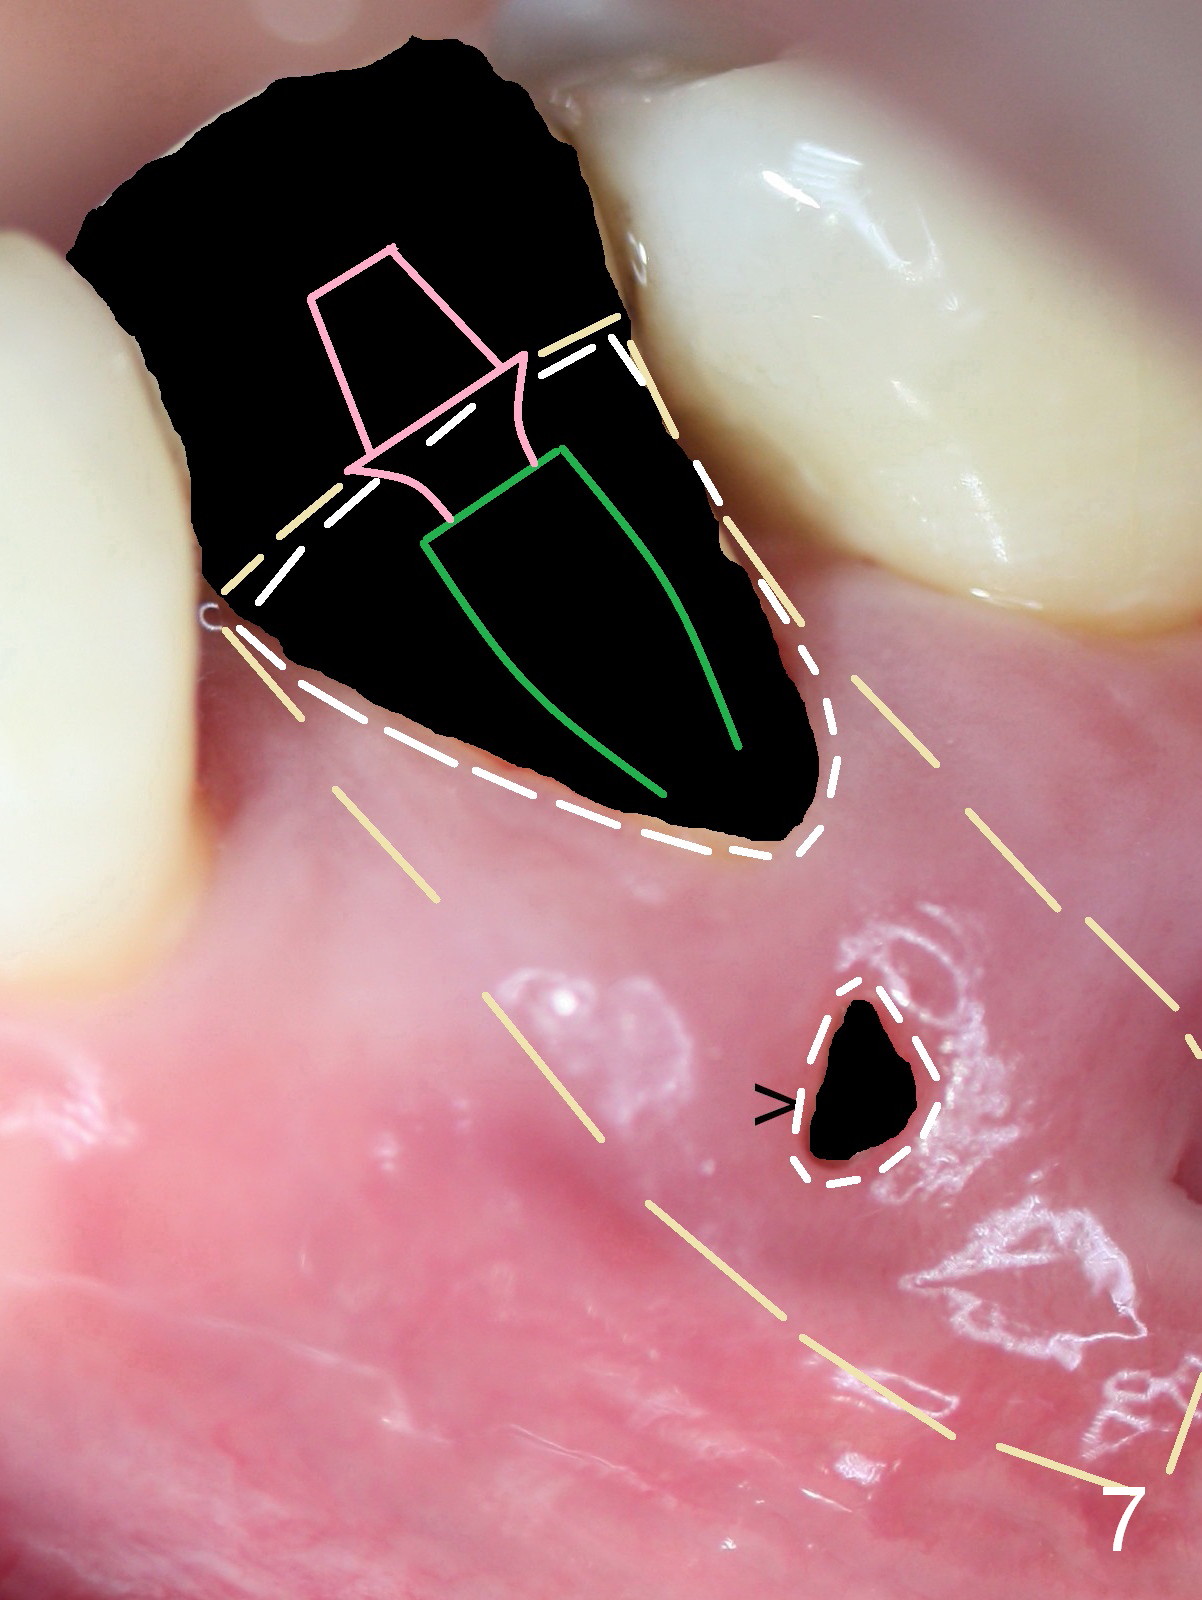

A 45-year-old man (JT) has endo failure at #20 with fenestration (Fig.1,2 black >) and fistula (white <). Insertion of a Gutta Percha at the fistula (Fig. 3 <; PA taken 2 years ago) indicates that the infection is dervied from the apex of the tooth #20. The socket will be soaked with 2% Xylo, 1:50,000 Epinephrine gauze. A 4.5x17 mm tissue-level (Fig.4) or 14 mm bone-level implant is placed as lingual as possible (Fig.5 green). If primary stability is achieved, an abutment is placed (pink). A large piece of resorbable membrane is used to cover the buccal defect (including buccal recession, fenestration and fistula (Fig.6 yellow dashed line). Two small pieces of non-resorbable membrane are placed to cover the gingival recession and the fenestration (Fig.7 white dashed line, buried underneath the edge of the gigniva). Then place bone graft buccally. Place a small piece of gauze (one layer) or plastic (from Tatum implant bag) over the 2nd membrane over the gingival recession and fabricate an immediate provisional. When the acrylic is partially set, remove the gauze or plastic from the provisional. After trimming and polishing, the provisional is cemented to securely keep the 2nd membrane in place. When the wound is healing and the 2nd membrane is stable, trim the buccal extension of the provisional. It is expected that the buccal hard and soft tissue will regenerate over the implant.